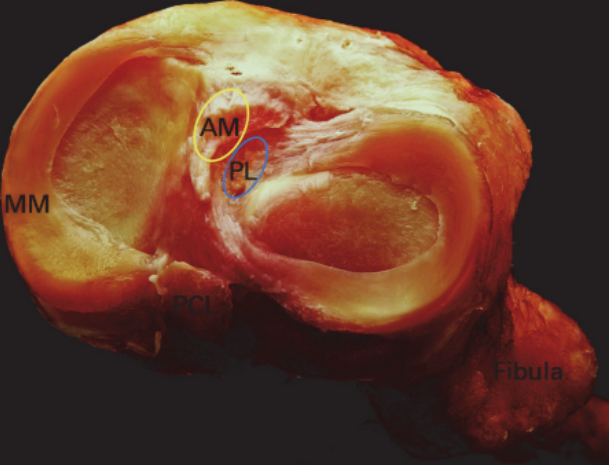

ACL 解剖

前交叉韧带起自股骨外侧髁的内侧面,斜向前下方,止于胫骨髁间隆起的前部。ACL 分为前内束(AM)和后外束(PL)。当屈膝 30° ~ 40° 时,前交叉韧带的张力最小。